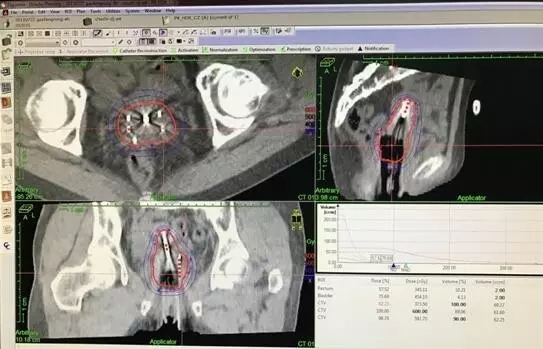

2015年6月19日-8月11日给予宫颈癌根治性同步放化疗(放疗靶区包括腹主动脉、盆腔淋巴引流区,子宫及全部阴道,调强放疗DT 5040cGy/28F,腹膜后及盆腔淋巴结同步加量至5992cGy。宫腔管+组织间插植DT3000cGy/5F。放疗期间同步顺铂周剂量化疗5周期)。放疗后宫颈肿瘤基本消退,阴道流血、分泌物消失,疼痛缓解。